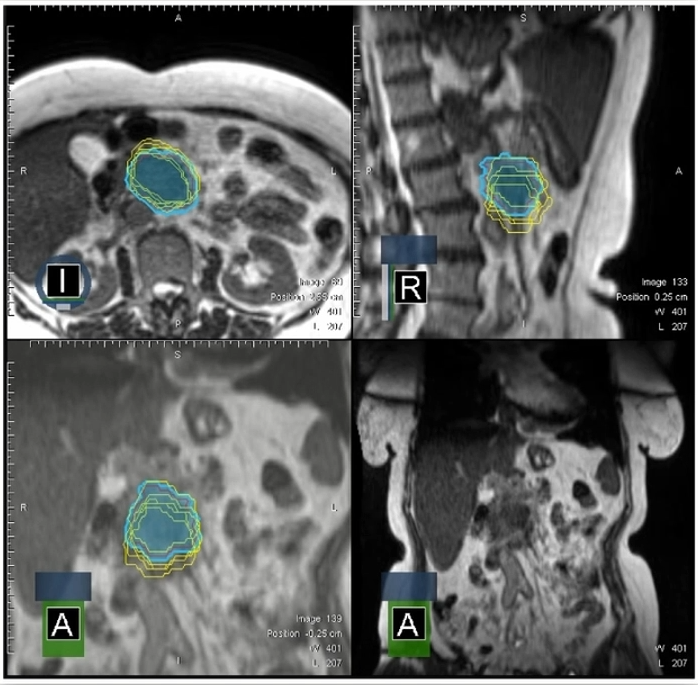

ͼ9 °Ñ5¸ö·Ö´Î²î±ðµÄGTV¹´»­¾ÙÐеþ¼Ó£¬£¬£¬£¬£¬£¬£¬·¢Ã÷ÔÚÒÈÏÙ°©SBRTµÄ5¸ö·Ö´ÎÖÎÁÆÊ±´ú£¬£¬£¬£¬£¬£¬£¬GTVµÄ¹´»­×ª±ä½Ï´ó

Dr. OzyarÌåÏÖ£¬£¬£¬£¬£¬£¬£¬Í¨¹ýÔÚÿ¸ö·Ö´Î×ö¼ÁÁ¿Õ¹Íû£¬£¬£¬£¬£¬£¬£¬·¢Ã÷ÈôÊÇʼÖÕʹÓÃÔ­ÍýÏëµÄ»°£¬£¬£¬£¬£¬£¬£¬GTVºÍPTV»á´ó·ù¶ÈÇ·Á¿£¬£¬£¬£¬£¬£¬£¬Í¨¹ýÔÚÏß×Ô˳ӦÍýÏëARTÄܾÀÕýÕâÒ»µã£¬£¬£¬£¬£¬£¬£¬Èçͼ10Ëùʾ¡£¡£¡£¡£¡£¡£¡£¡£

ͼ 10?ͨ¹ýÔÚÿ¸ö·Ö´Î×ö¼ÁÁ¿Õ¹Íû£¬£¬£¬£¬£¬£¬£¬·¢Ã÷ÈôÊÇʼÖÕʹÓÃÔ­ÍýÏëµÄ»°£¬£¬£¬£¬£¬£¬£¬GTVºÍPTV»á´ó·ù¶ÈÇ·Á¿£¬£¬£¬£¬£¬£¬£¬Í¨¹ýÔÚÏß×Ô˳ӦÍýÏëARTÄܾÀÕýÕâÒ»µã